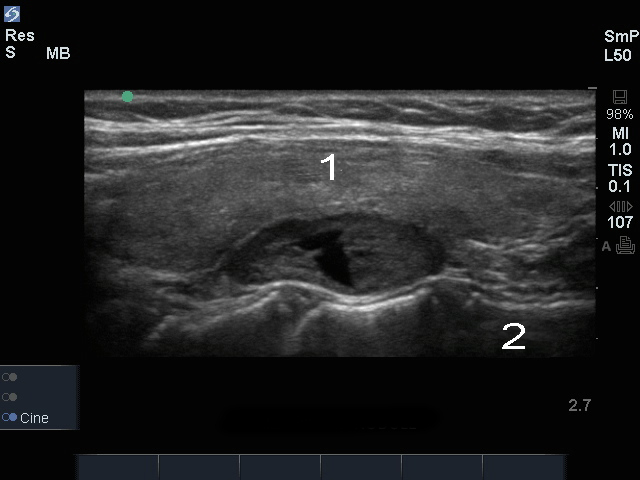

甲状腺副甲状腺結節画像

甲状腺

頸椎